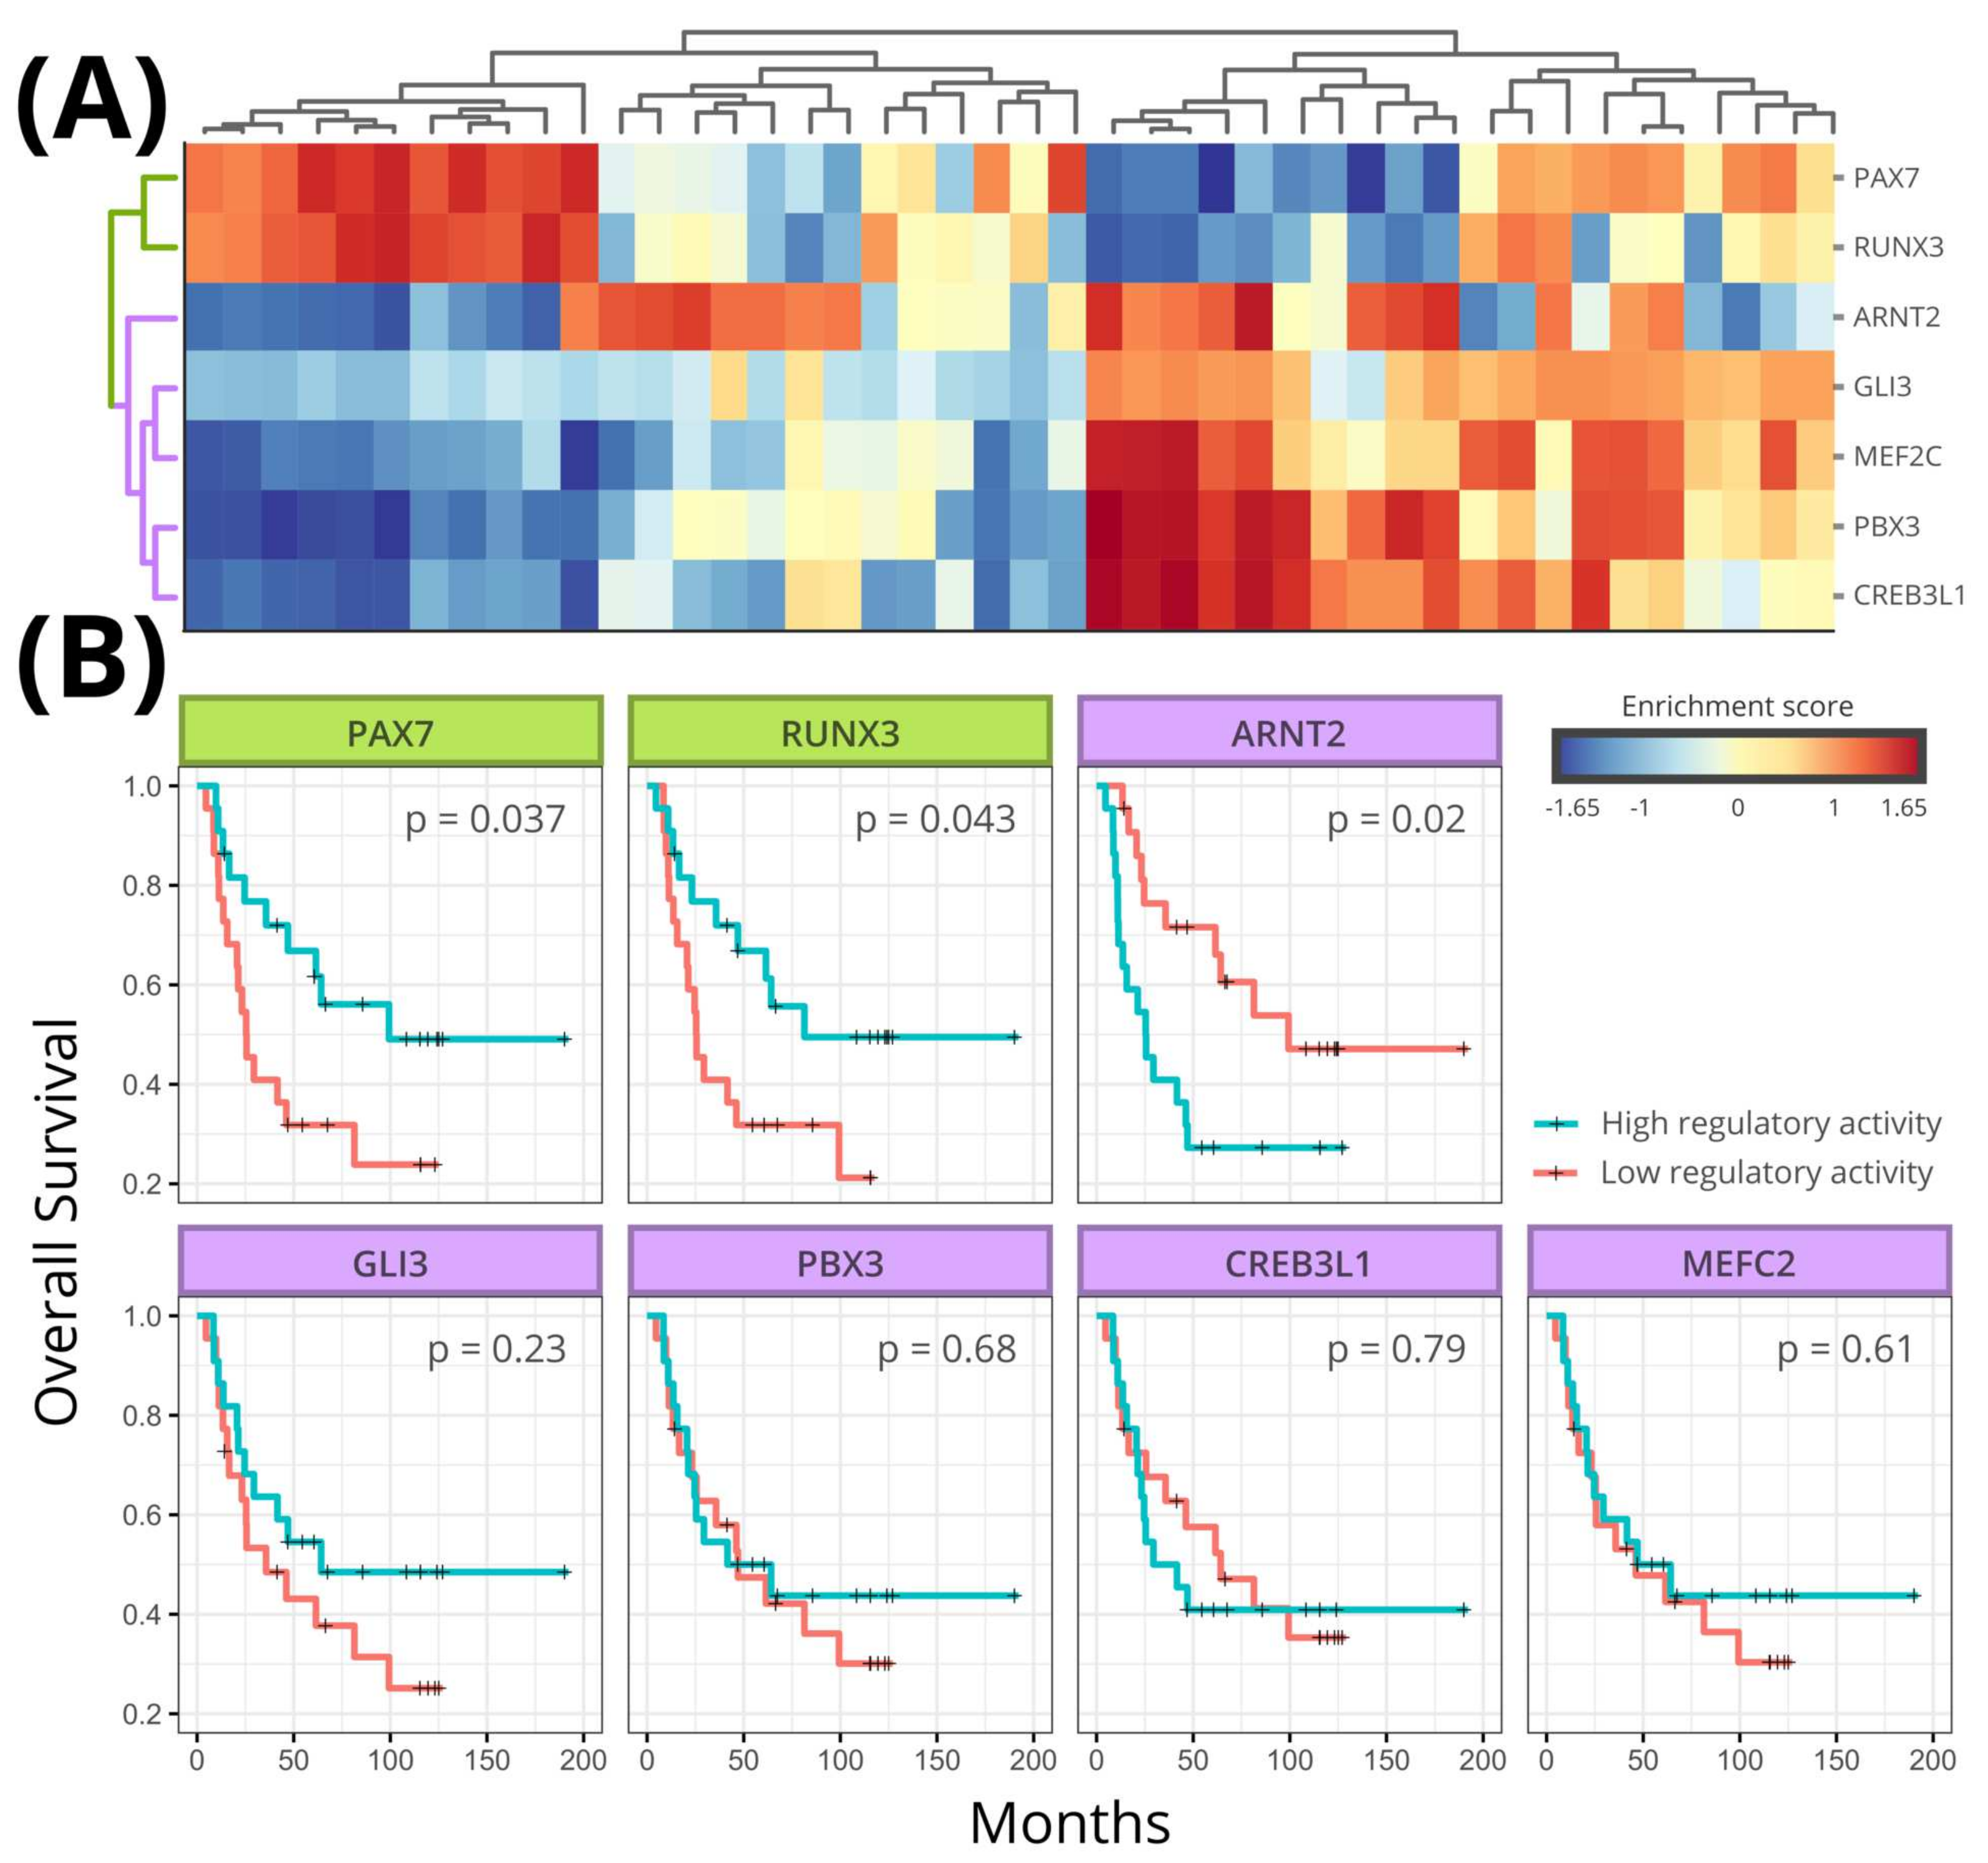

3.4. Regulon Activity

3.5. Survival Analysis